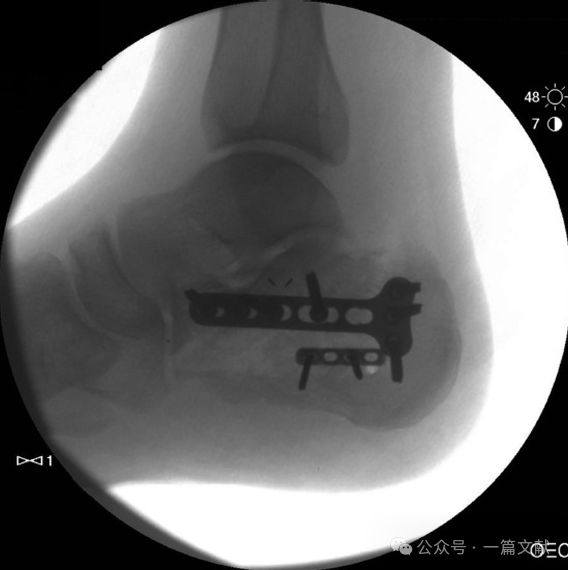

四,术中拍摄的各影像图如下: